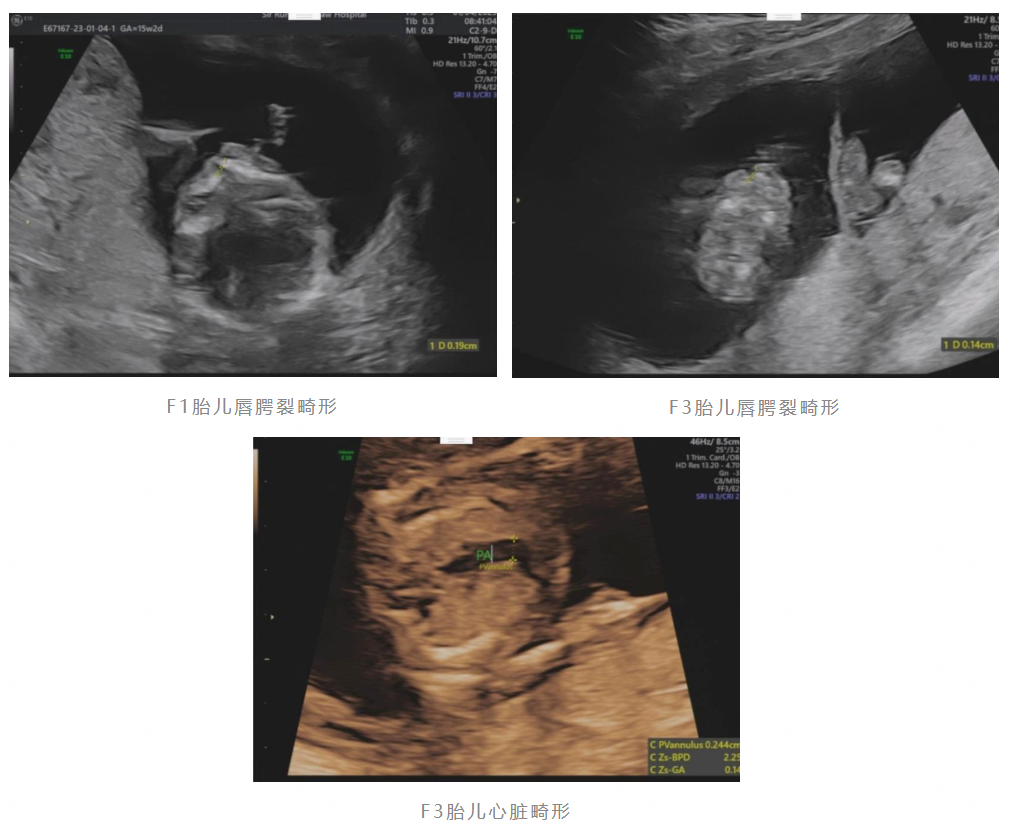

双胞胎共用一个心要不要生